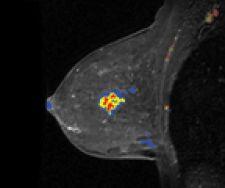

Confirma’s next-generation product for breast MRI includes a new customizable BI-RADS-centric user interface that accommodates a variety of user experience levels. Additional CADstream enhancements include improved 3D renderings and tools for morphology reporting.

The next generation of CADstream for breast MRI enhancements will include a customizable BI-RADS-centric user interface and improved volume summaries and morphology reporting tools. Additionally, the company will debut the Access Breast Coil with high quality diagnostic capability, flexible interventional access and optimized patient comfort.